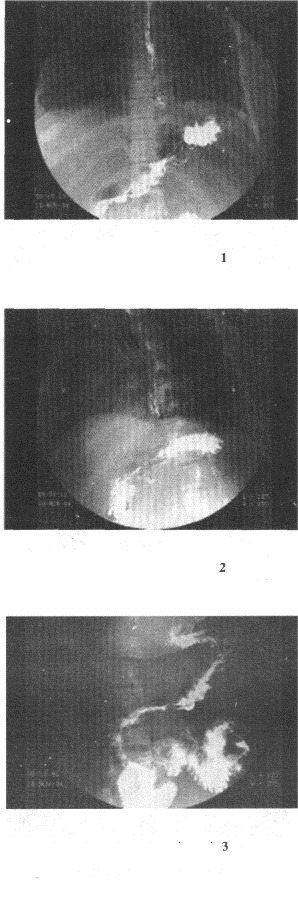

2.女,23歲,反復上腹部疼痛伴黑便2年余,嘔吐3天。有血吸蟲病史,曾行脾臟切除。結合圖像,最可能的診斷為

正確答案:C 解題思路:食管下段黏膜皺襞增粗、紆曲,呈串珠狀,結合患者病史,考慮食管胃底靜脈曲張。

3.女,73歲,吞咽困難2個月。體檢:咽充血,濾泡增生,最可能的診斷為

正確答案:C 解題思路:食管上段有充盈缺損表現,管腔狹窄,結合病史考慮食管癌可能。